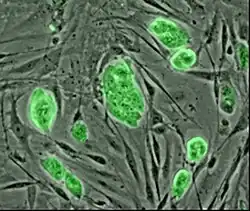

Nearly all research to date has made use of mouse embryonic stem cells (mES) or human embryonic stem cells (hES) derived from the early inner cell mass. Both have the essential stem cell characteristics, yet they require very different environments in order to maintain an undifferentiated state. Mouse ES cells are grown on a layer of gelatin as an extracellular matrix (for support) and require the presence of leukemia inhibitory factor (LIF) in serum media. A drug cocktail containing inhibitors to GSK3B and the MAPK/ERK pathway, called 2i, has also been shown to maintain pluripotency in stem cell culture.[25] Human ESCs are grown on a feeder layer of mouse embryonic fibroblasts and require the presence of basic fibroblast growth factor (bFGF or FGF-2).[26] Without optimal culture conditions or genetic manipulation,[27] embryonic stem cells will rapidly differentiate.

A human embryonic stem cell is also defined by the expression of several transcription factors and cell surface proteins. The transcription factors Oct-4, Nanog, and Sox2 form the core regulatory network that ensures the suppression of genes that lead to differentiation and the maintenance of pluripotency.[28] The cell surface antigens most commonly used to identify hES cells are the glycolipids stage specific embryonic antigen 3 and 4, and the keratan sulfate antigens Tra-1-60 and Tra-1-81. The molecular definition of a stem cell includes many more proteins and continues to be a topic of research.[29]

By using human embryonic stem cells to produce specialized cells like nerve cells or heart cells in the lab, scientists can gain access to adult human cells without taking tissue from patients. They can then study these specialized adult cells in detail to try to discern complications of diseases, or to study cell reactions to proposed new drugs.

Because of their combined abilities of unlimited expansion and pluripotency, embryonic stem cells remain a theoretically potential source for regenerative medicine and tissue replacement after injury or disease.,[30] however, there are currently no approved treatments using ES cells. The first human trial was approved by the US Food and Drug Administration in January 2009.[31] However, the human trial was not initiated until October 13, 2010, in Atlanta for spinal cord injury research. On November 14, 2011, the company conducting the trial (Geron Corporation) announced that it will discontinue further development of its stem cell programs.[32] Differentiating ES cells into usable cells while avoiding transplant rejection are just a few of the hurdles that embryonic stem cell researchers still face.[33] Embryonic stem cells, being pluripotent, require specific signals for correct differentiation – if injected directly into another body, ES cells will differentiate into many different types of cells, causing a teratoma. Ethical considerations regarding the use of unborn human tissue are another reason for the lack of approved treatments using embryonic stem cells. Many nations currently have moratoria or limitations on either human ES cell research or the production of new human ES cell lines.

Human embryonic stem cell colony on mouse embryonic fibroblast feeder layer

Human embryonic stem cell colony on mouse embryonic fibroblast feeder layer